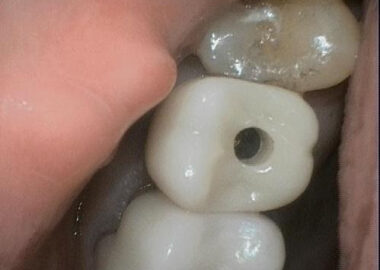

Following a detailed discussion of the retrieval algorithm, the site was infiltrated, and a conservative exposure was made of the implant top, avoiding the existing sutures from the prior recent flap procedure. The initial preoperative photo shows the extent of the previous effort, where a slot strategy was attempted into the top of the screw fragment but also into the top aspect of implant adjacent to the start of the implant threads. This screw fragment was residing slightly below the first implant thread and was non-mobile so in my treatment algorithm it was classified as a Type IV case which required a concentric mobilization technique. The center of the screw fragment was identified and spotted with a custom prototype guide and specific custom spotting drill and modified until it was concentric enough to safely proceed with the actual drilling. The drilling protocol was initiated at .8mm and was taken completely through the fragment. A modified ratchet drive easy-out type screw extractor was then engaged and with considerable force the fragment was delivered intact. A M1.6 tap was chased through the treads to ensure continuity and a Straumann healing abutment was placed finger tight. The patient was referred back to Dr. L. to continue with the restorative phase. Even though there was prior damage to the implant from the original recovery effort, going forward, the prognosis for this implant remains unchanged secondary to this event or recovery efforts as the damage occurred in essentially a non-critical area between the critical top indexing and the lower threaded areas. The patient was very pleased with the successful outcome.

So why did this screw fail? Examination of the crown lead to the answer. The initial clue was the looseness that was felt after initial torqueing. As the crown was present at this appointment, it was tried onto an RC analog and found to be very loose fitting even though the custom prototype RC drill guide fit the implant very well, confirming the RC implant interface. However, when tried onto an NC analog it fit with precision. Obviously, this was an error with the wrong size abutment interface. As both NC and RC platforms utilize the same M1.6 diameter screw, it is possible to thread in an NC screw into an RC implant. Unfortunately, that’s where the compatibility ends. The NC platform has a smaller crossfit connection and the NC abutment screw actually bottoms out before the head of the screw engages the screw seat. This allows all of the total torque placed on the screw to become thread torque with none bleeding off in the screw head seat. The screw fragment is essentially driven and wedged into the bottom of the implant wedging between the bottom and the last implant thread at full torque before fracture. This is why retrieving a fragment like this one often results in having to recover the screw fragment in pieces depending on the amount of torque the recovery tools can deliver. We were definitely fortunate to recover this fragment in one piece, but we were also prepared to proceed to a total drill out with the protocol we were following.